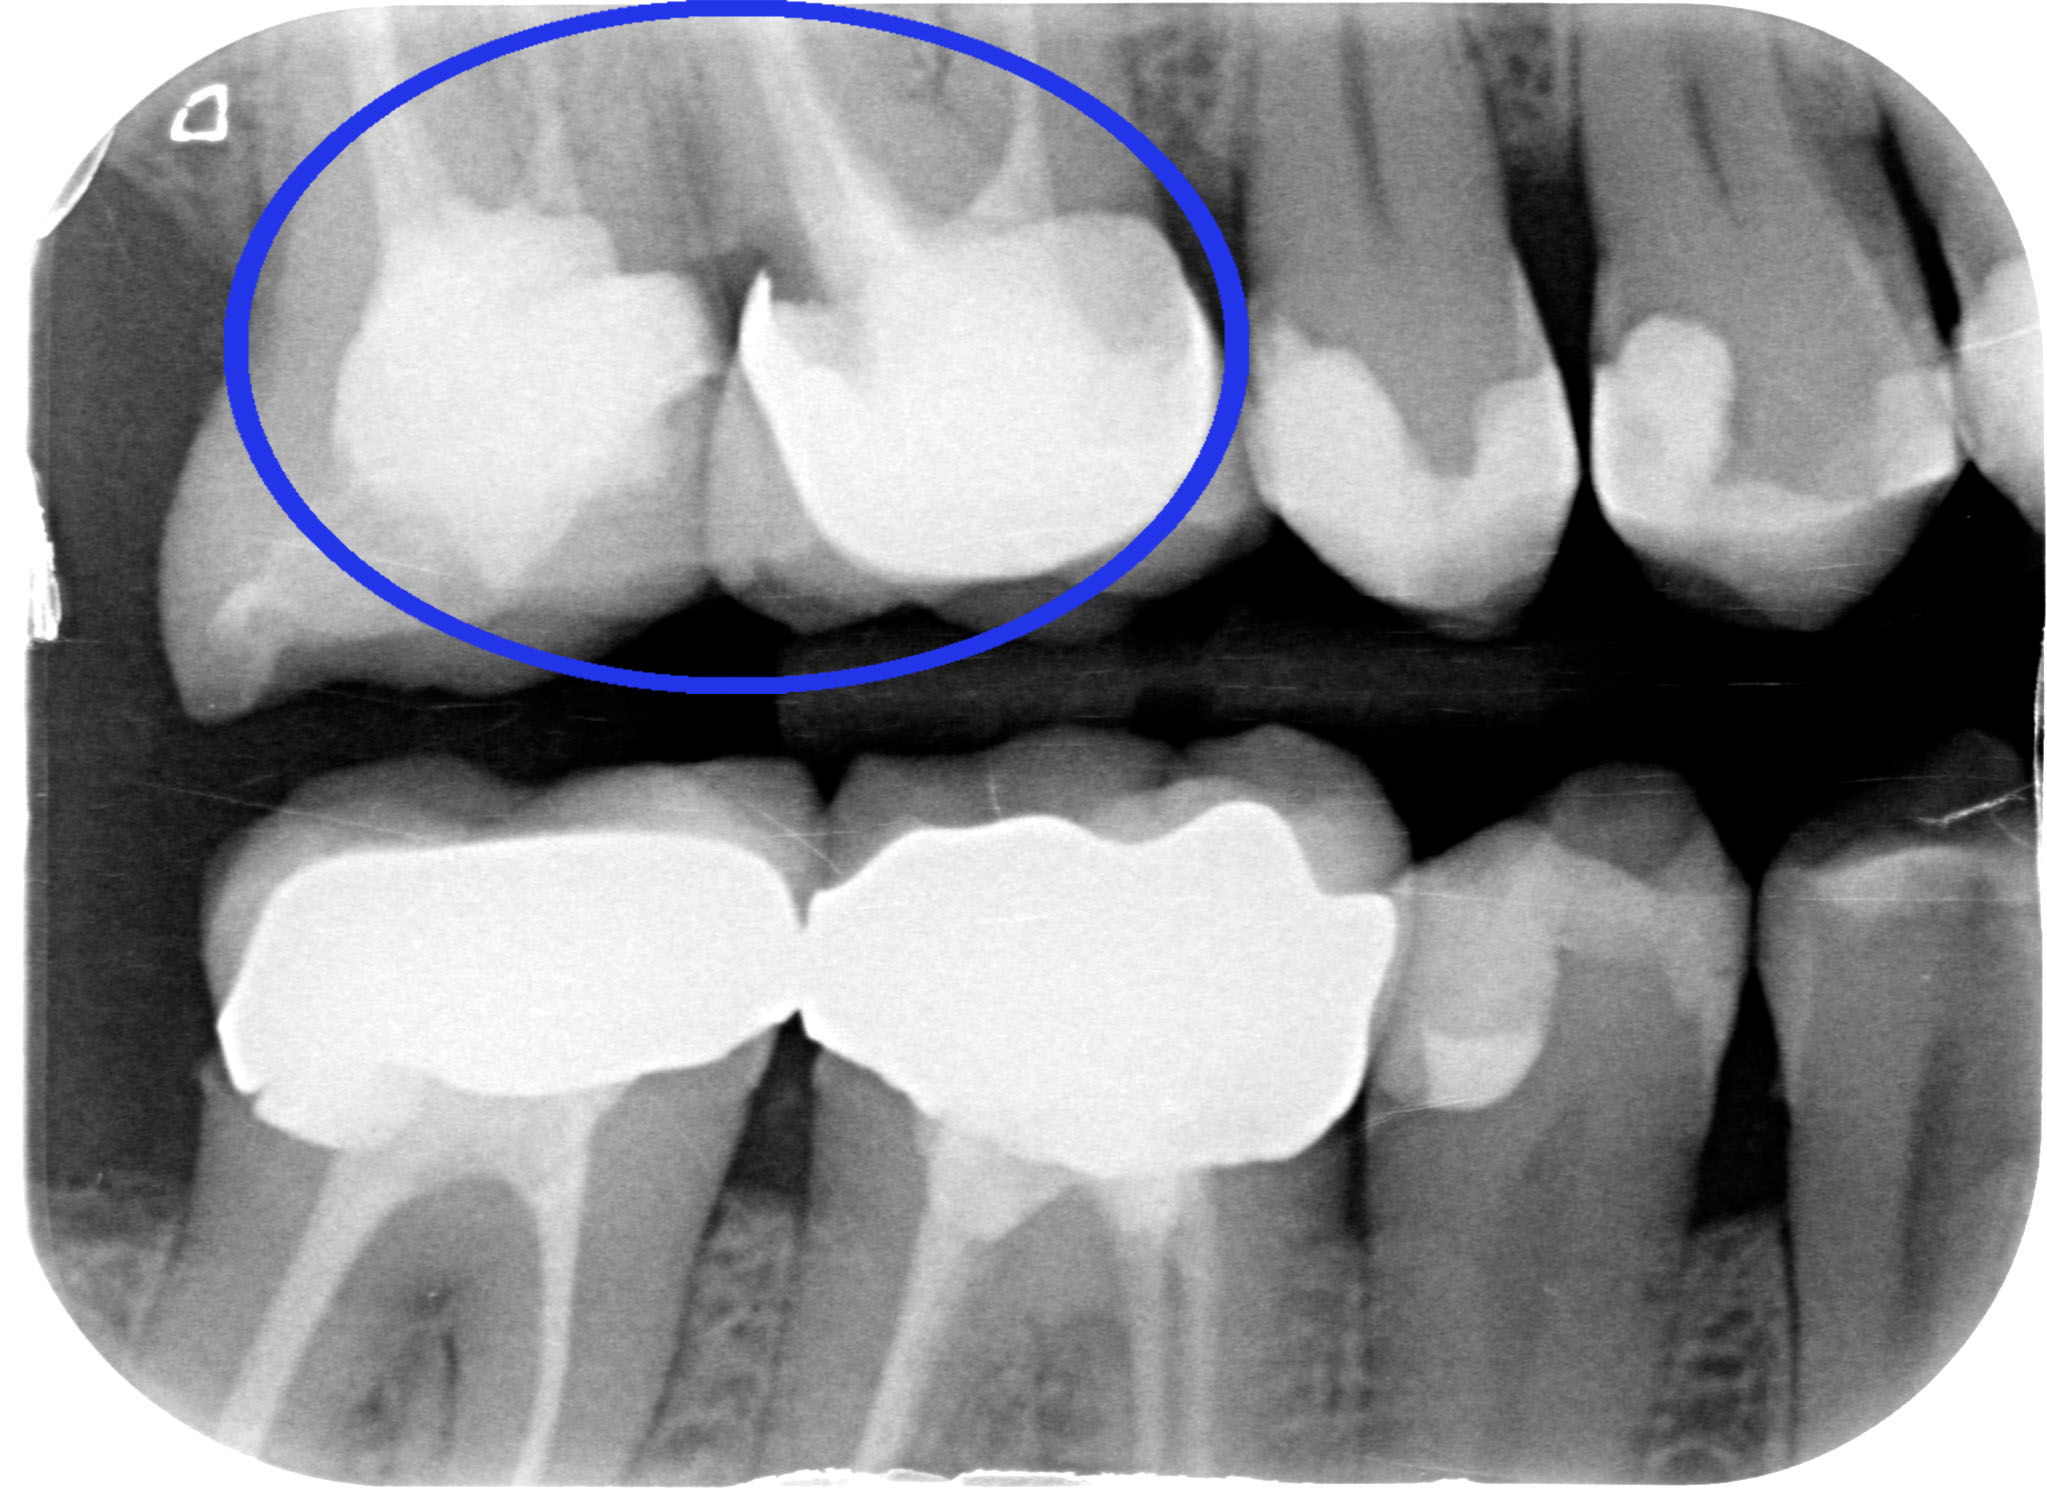

Accademicamente potremmo dire: CARIE SECONDARIA A CARICO DI 1.6 PRECEDENTEMENTE RESTAURATO MEDIANTE CORONA IN METALLO CERAMICA.

Ma io nella mia testa dico “chi ha fatto quella corona avrebbe dovuto fare un allungamento di corona clinica, ma non lo sapeva o non lo voleva fare. Quindi non ha potuto gestire correttamente il margine di chiusura distale. Quindi è rimasto del tessuto cariato o non è stato effettuato un corretto sigillo marginale per cui… E’ SUCCESSO IL FATTACCIO!”

Anche se il paziente non avvertiva nessun fastidio abbiamo fatto una visita completa,                che comprende le due bite-wings posteriori e ci siamo accorti del problema. Ora però lo dobbiamo risolvere. Abbiamo tre strade: